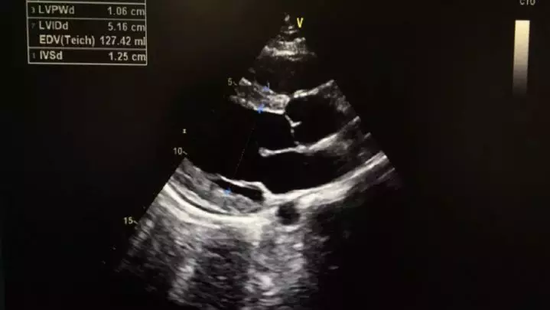

在杭州打工的父母听说儿子的事情急坏了,11月1日,小张父母将小张接到了杭州,送到浙大一院急救中心进行诊治,经过胸部CT、心电图和心脏彩超检查,发现小张的心电图ST段抬高,心肌酶谱中血清肌钙蛋白含量也高出了正常人近400倍,心肌受损情况严重;

收缩期

舒张期

在急救中心,小张进行了五天的糖皮质激素输液,并转到心内科做进一步治疗,在浙大一院经过十天的抗生素输液治疗和营养心肌的药物辅助,目前小张的心电图、心超、心脏功能等已恢复正常。